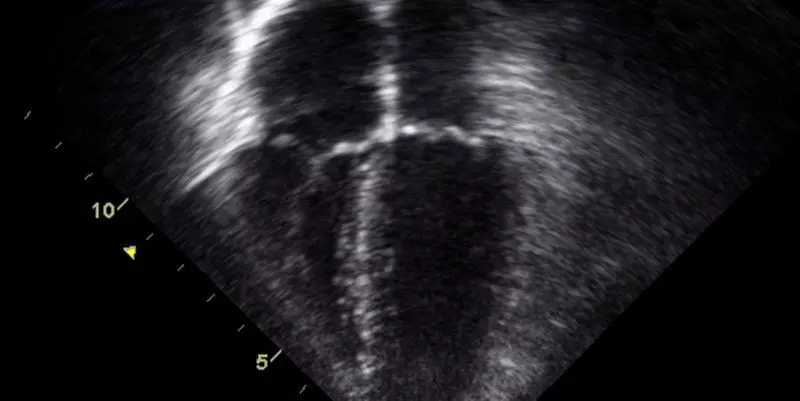

Unlocking Better Outcomes: How Focused Transthoracic Echocardiography Transforms ICU Care After Cesarean Section

FTTE is a point-of-care ultrasound tool that allows clinicians to rapidly assess cardiac function at the bedside. In the context of post-CS ICU admissions, FTTE helps differentiate between cardiac and non-cardiac causes of shock and respiratory distress—conditions that often masquerade as routine postpartum changes. By offering real-time, non-invasive insight into the heart’s status, FTTE enables targeted interventions, potentially saving lives.

This prospective, observational cohort study included 60 post-CS patients admitted to the ICU within 42 days of delivery at a tertiary care center. FTTE was performed in patients with suspected cardiac disturbances, unresolved clinical dilemmas, or significant hemodynamic or respiratory instability. Cardiology residents, using advanced ultrasound equipment, performed the scans. FTTE findings were used to confirm, refine, or rule out cardiac pathologies and guide subsequent management.